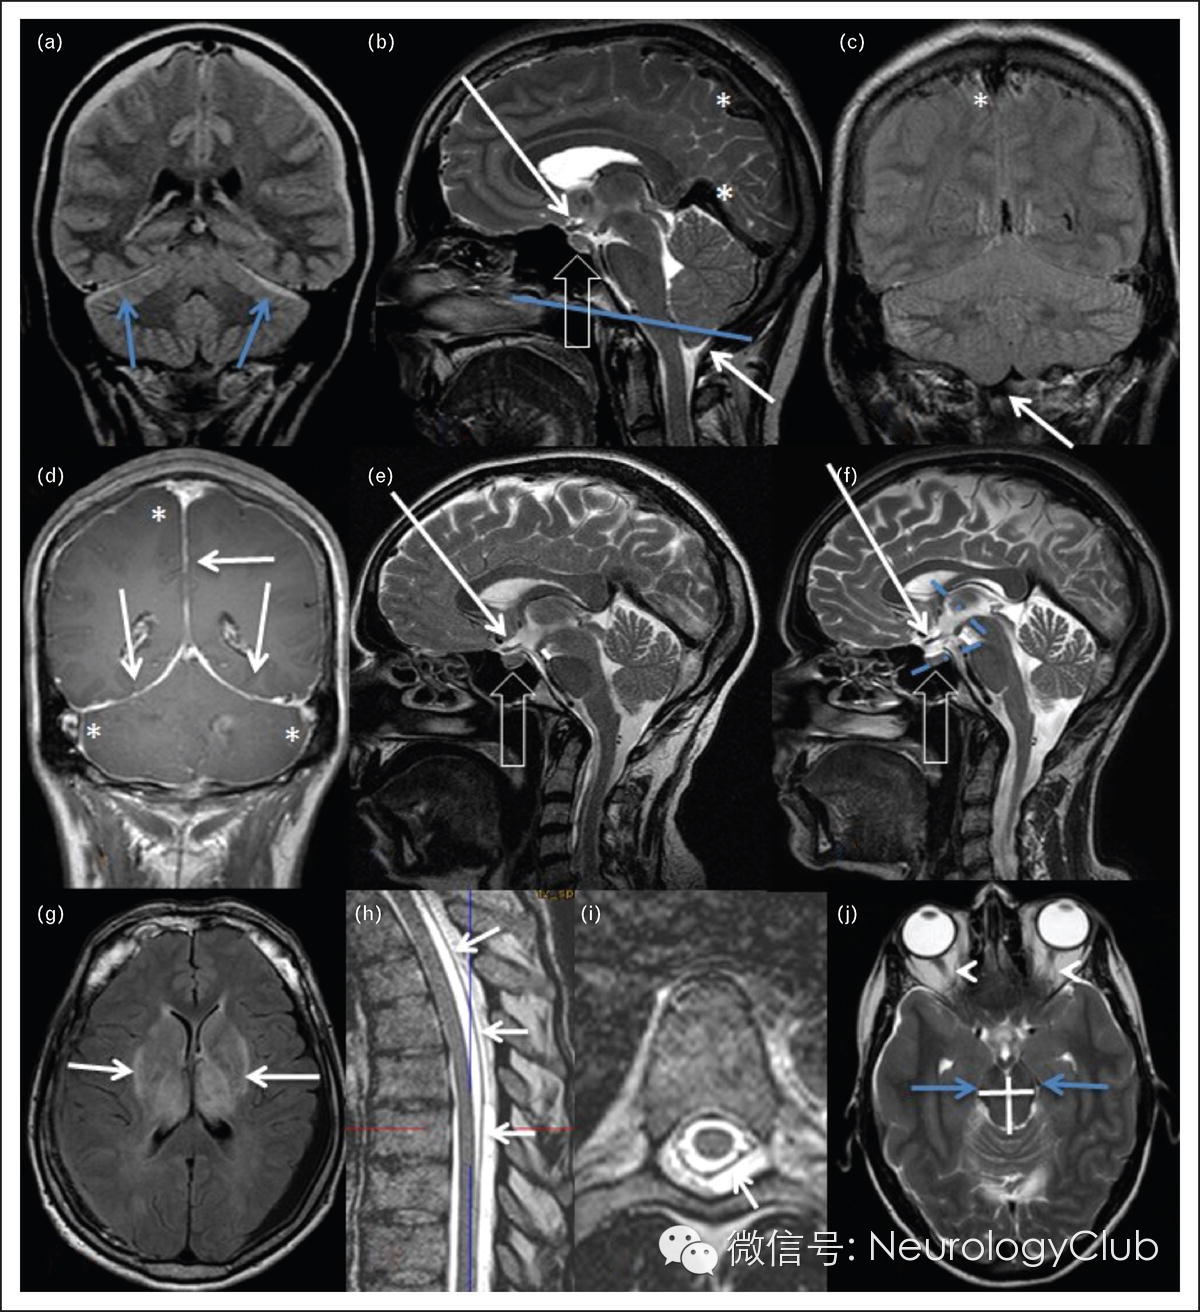

图1 低颅压的MRI征象

沿着大脑凸面和小脑幕可见硬膜下积液(图a)。静脉窦充血(* 图b,c,d)。小脑扁桃体下垂(白箭,图b,c)。脑膜增厚强化(箭,图d)。垂体肿大(空心箭,图b,e为血贴术前,图f为血贴术后)。脑干下垂,周边环绕脑脊液减少(蓝箭)乳头体肿大挤压脑池,导致乳头体脑桥距离缩小(虚线,图e,f),视神经下垂(长箭,图e,f)。脑桥中脑角变窄(蓝色虚线,图f),硬膜外血贴术前(图e)后(图f)。基底节区对称性信号改变(箭,图g)。硬脊膜和硬膜外积液的识别(箭,图h,i)。中脑的前后径变长,左右距离变短(交叉线,图i)视神经鞘空虚(箭,图i)。